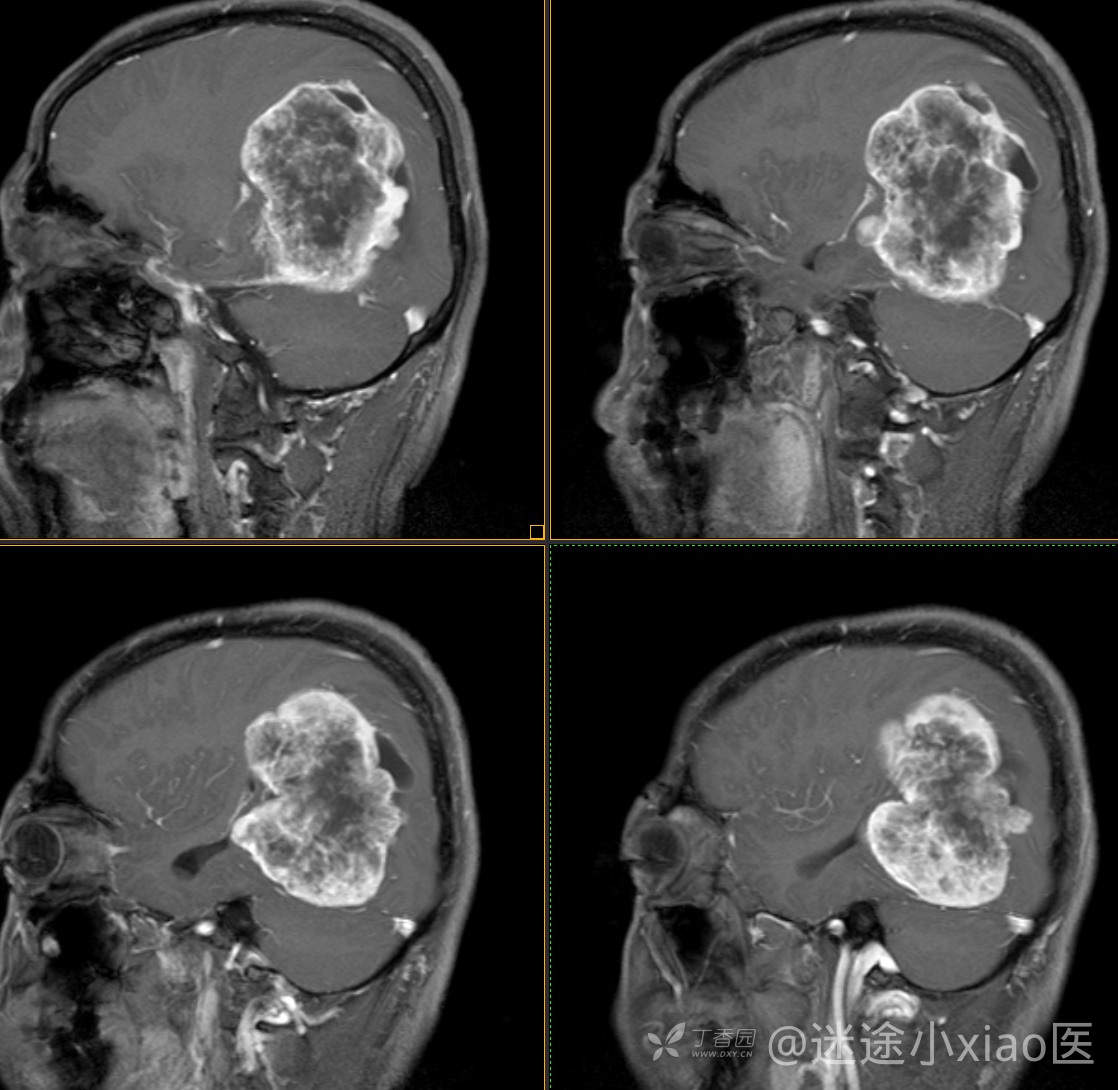

患者年龄:43

患者性别:男

简要病史:头痛3月余,查体无殊